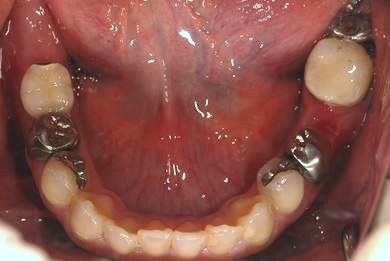

インプラントの症例写真 IMPLANT

インプラント治療

| 性別/年齢 | 女性 / 34歳 | ||||||||||||||||||||||||||||||||

| 主訴 | 左上奥の歯茎の腫れと、口臭などが気になっています。 | ||||||||||||||||||||||||||||||||

| 治療方針 | 右下奥欠損部分をインプラント治療にて機能的・審美的回復を行う。 | ||||||||||||||||||||||||||||||||

| 治療内容 | インプラント1本、メタルボンドセラミッククラウン1本 | ||||||||||||||||||||||||||||||||

| 総治療費 | 252,000円 | ||||||||||||||||||||||||||||||||

| 治療期間 | 4ヶ月 |